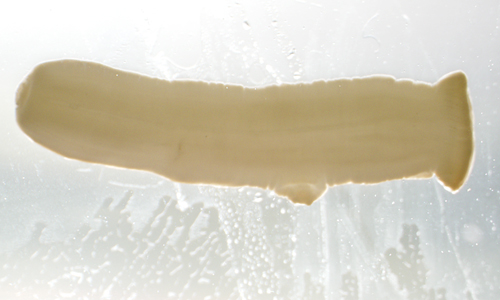

The DPDx Team received a pair of proglottids from a state health lab for cestode confirmation and identification. The specimens were submitted in 70% ethanol and measured on average 12.0 mm long by 3.0 mm wide. The proglottids were reportedly found in the feces of a 43-year-old woman with no documented international travel. Figures A and B show one of the proglottids. Figures C and D show the same proglottid after soaking in lactophenol for several hours. What is your diagnosis? Based on what criteria?

Figure A